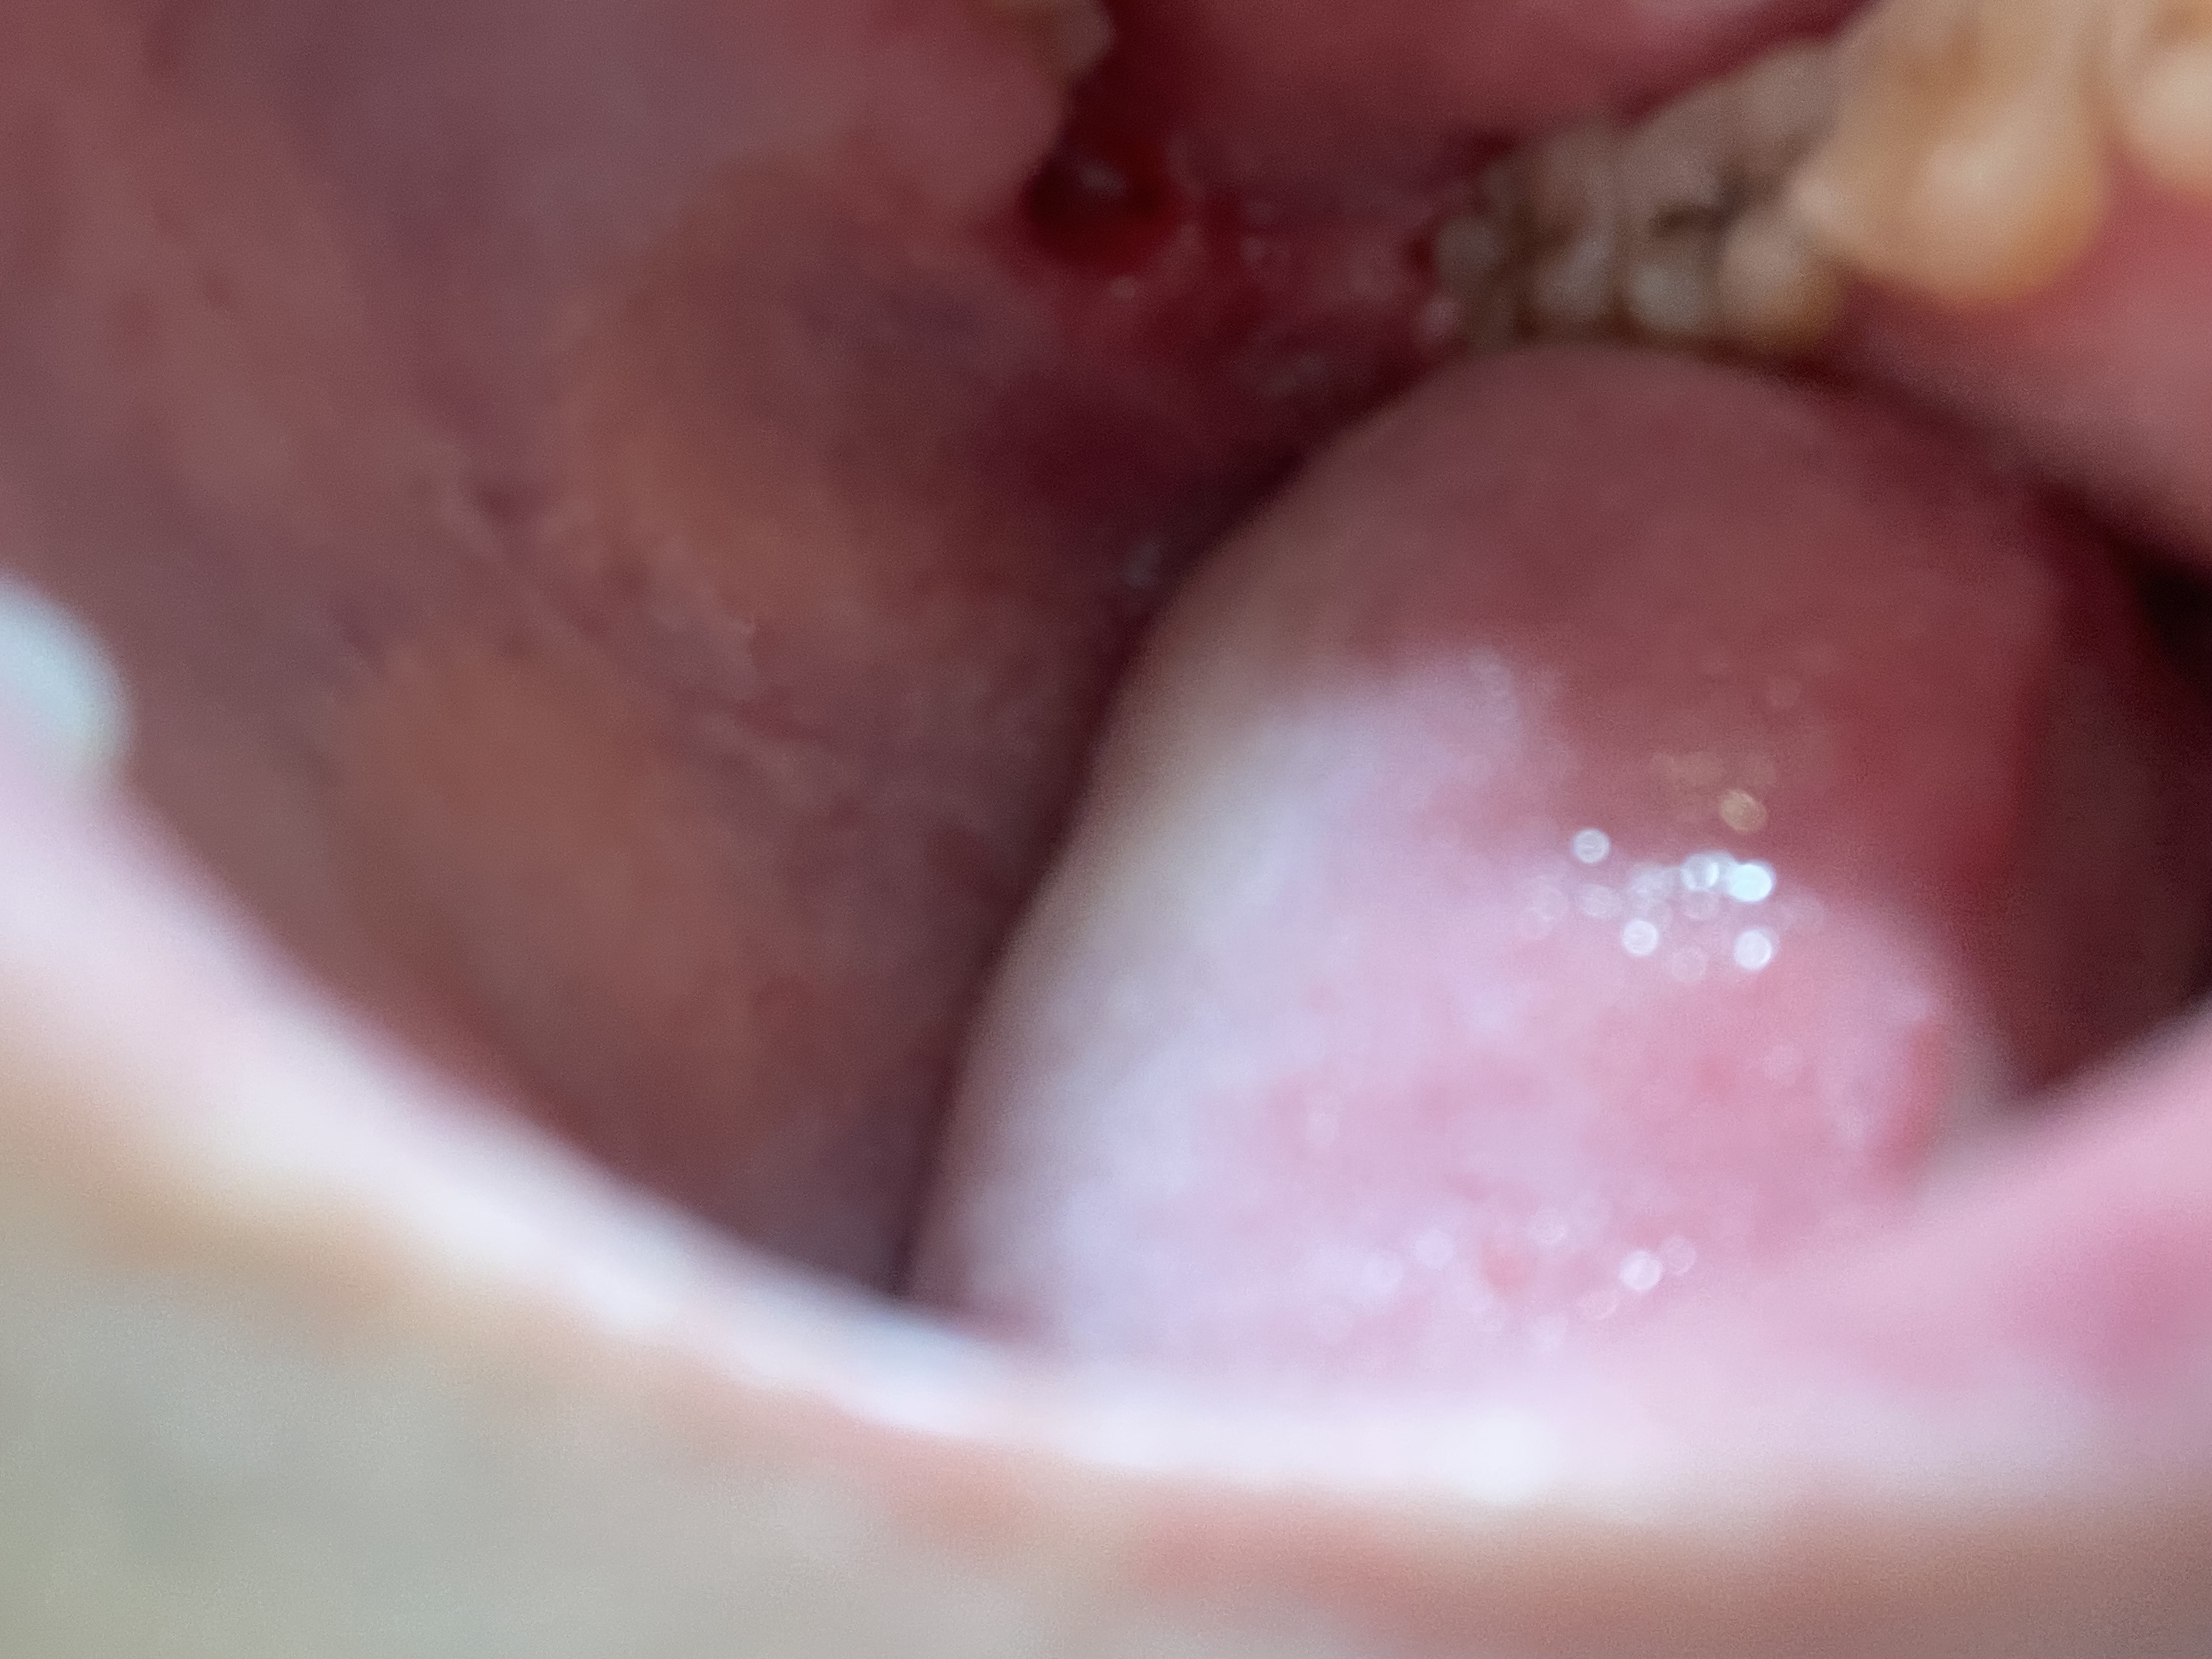

奥歯の真後ろに歯茎が割けているようなすき間があります。